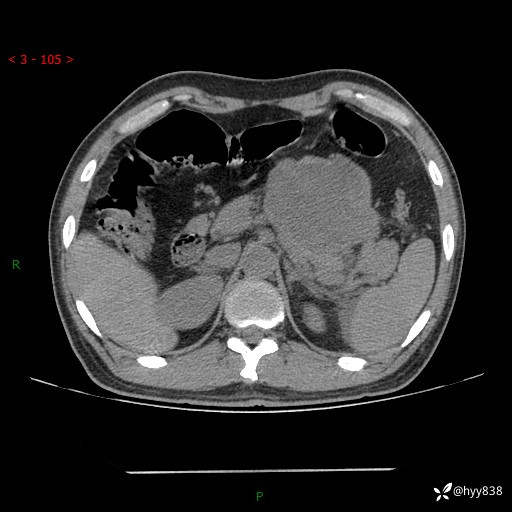

病例39岁/女,左侧腰痛入院。腹腔囊实性肿块,定位、定性---结果公布~

性别:男

年龄:39岁

简要病史:左侧腰痛待查,CT发现腹腔占位

腹部CT平扫+增强